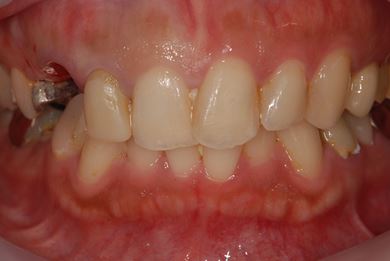

| 性別/年齢 | 女性 / 29歳 | ||||||||||||||||||||||||||||||||

| 治療方針 | 抜歯と同時にインプラント埋入を行い、治療期間を短縮する。 | ||||||||||||||||||||||||||||||||

| 治療内容 | インプラント2本(抜歯即日スピードインプラント)、ハイブリッドセラミッククラウン3本 | ||||||||||||||||||||||||||||||||

| 治療期間 | 8ヶ月 |